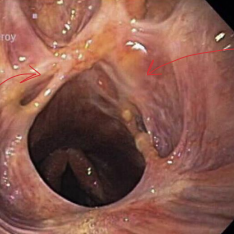

Mycosis

Et: Aspergillus, plaques near arteries/nerves

Cs: aneurysm, rupture, epistaxis (fatal), neuropathy, aspiration, cough, dysphagia, Horners

Tx: stabilize hemorrhage, sx arterial occlusion (balloon/coil), antifungals

Empyema

Et: strangle, carrier state

Cs: Purulent exudate, nasal discharge, fever, depression, airway obx

Dt: endoscopy, culture/PCR

Tx: lavage, antibiotics, Sx removal, Modified Whitehouse procedure (ventral drainage)